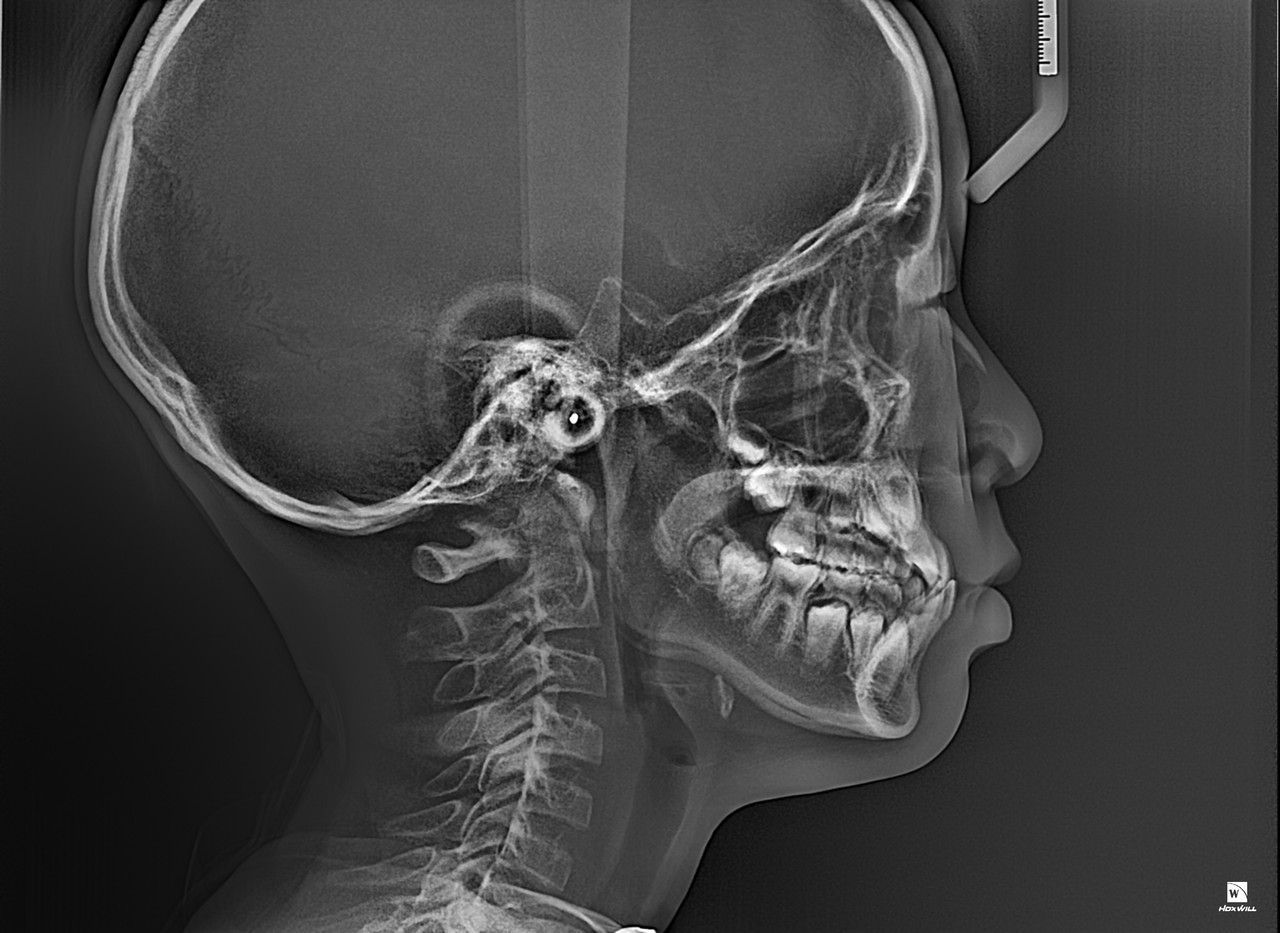

1차 교정(Phase I Orthodontic Treatment)은 혼합 치열기(유치와 영구치가 같이 있는 시기)

또는 초등학교 저학년~중학교 초반 정도의 어린 나이에 진행되는 초기 교정 치료입니다.

목표는 턱의 성장 조절, 심각한 부정교합 예방, 공간 확보, 습관 개선 등 입니다.